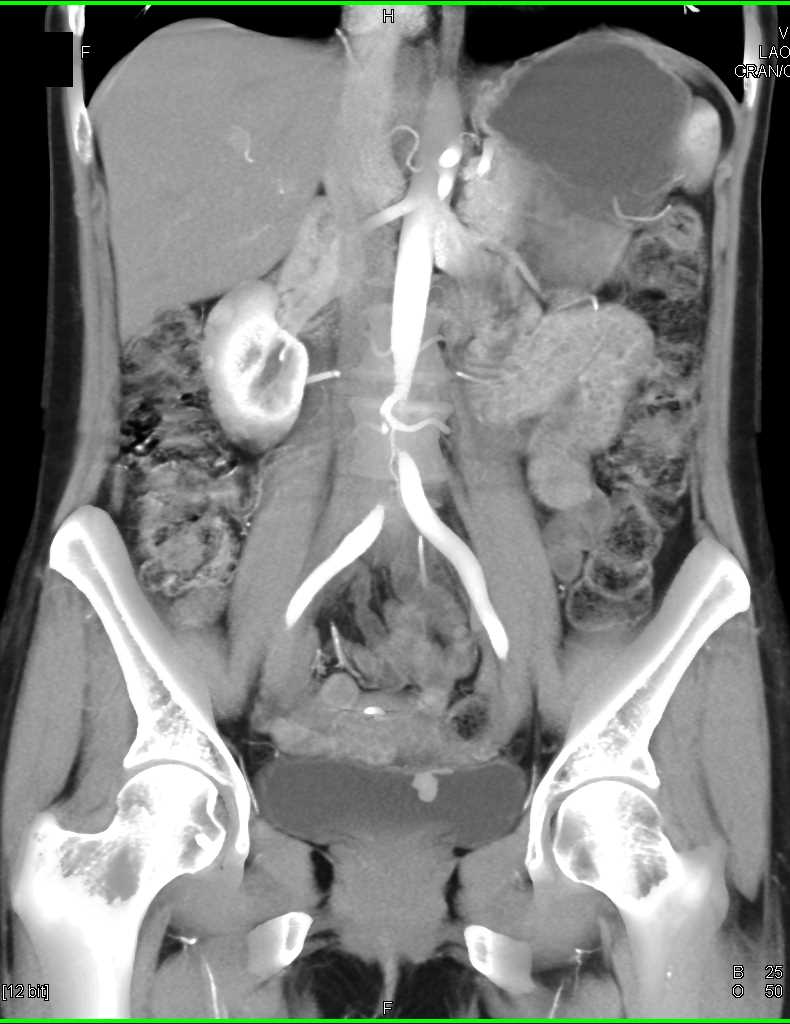

Urachal Carcinoma of the Bladder